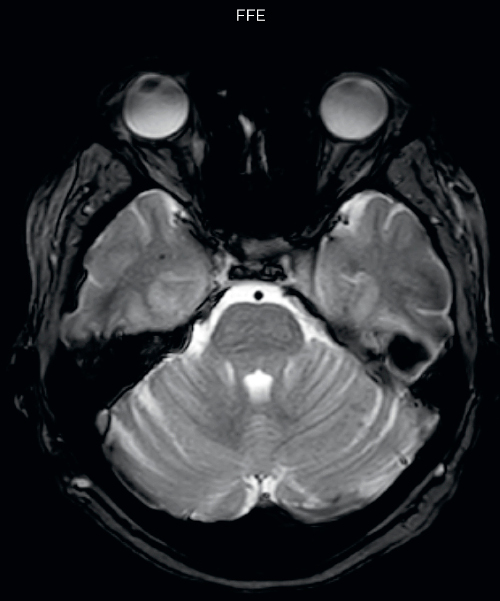

Hemosiderin foci in brain

Gradient echo imaging and SWIp are compared in a patient with radiation-induced foci of hemosiderin deposition. A greater number of small foci is seen on the SWIp image. Ingenia 3.0T